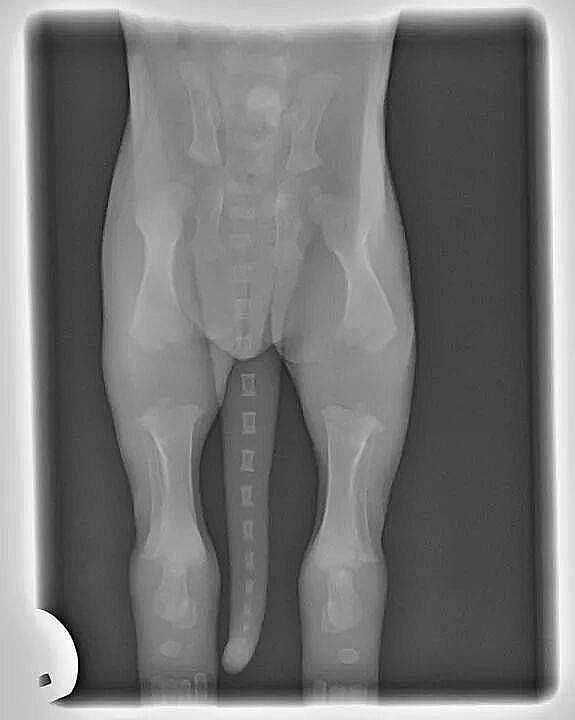

Op deze foto ziet u een röntgenfoto van een 2 weken oude pup.

Zie hoe de botten nog moeten groeien voordat ze goede gewrichten vormen.

Dat is de reden waarom je puppy's nooit moet laten springen,

de trap of bank op- en af laten lopen, teveel (los) laten lopen of trainen.

Teveel beweging op jonge leeftijd leidt tot serieuze problemen later in het leven van de hond !!!